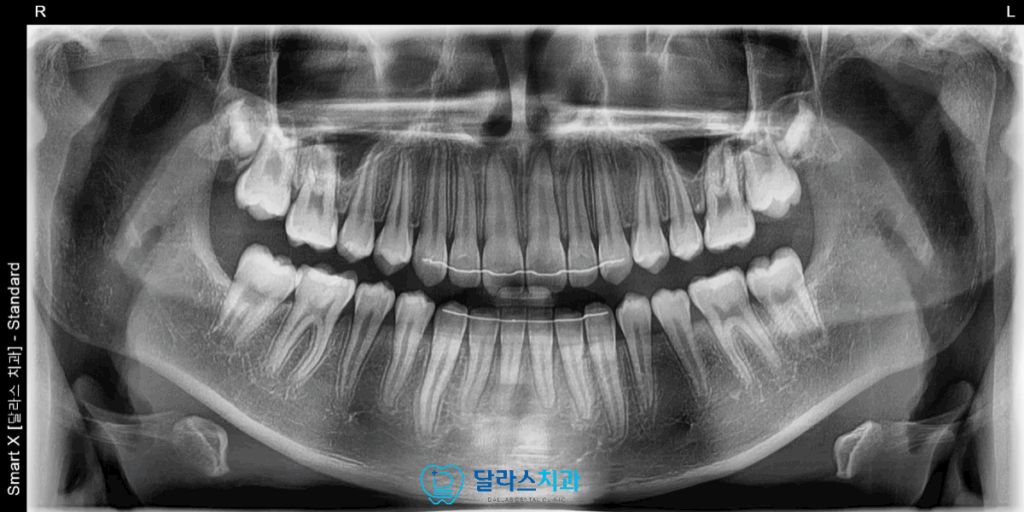

노원치과에서 교정을 진행하는 동안 유치가 빠지고 영구치가 모두 맹출되었으나

이미 인비절라인을 통한 각 시기별 맞춤 제작 장치로

자연스럽게 넘어가면서 최종적으로는 영구치열이 모두 가지런하게 배열되었습니다.

Invisalign First와 고무줄의 병행 치료를 통해 발치나 스크류 없이도

Class I 교합 관계 획득과 돌출입 개선이 가능했으며

성장기 아동에서의 성장 중 치료 개입이 갖는 큰 이점을 다시 한번 확인할 수 있는 과정이었습니다.